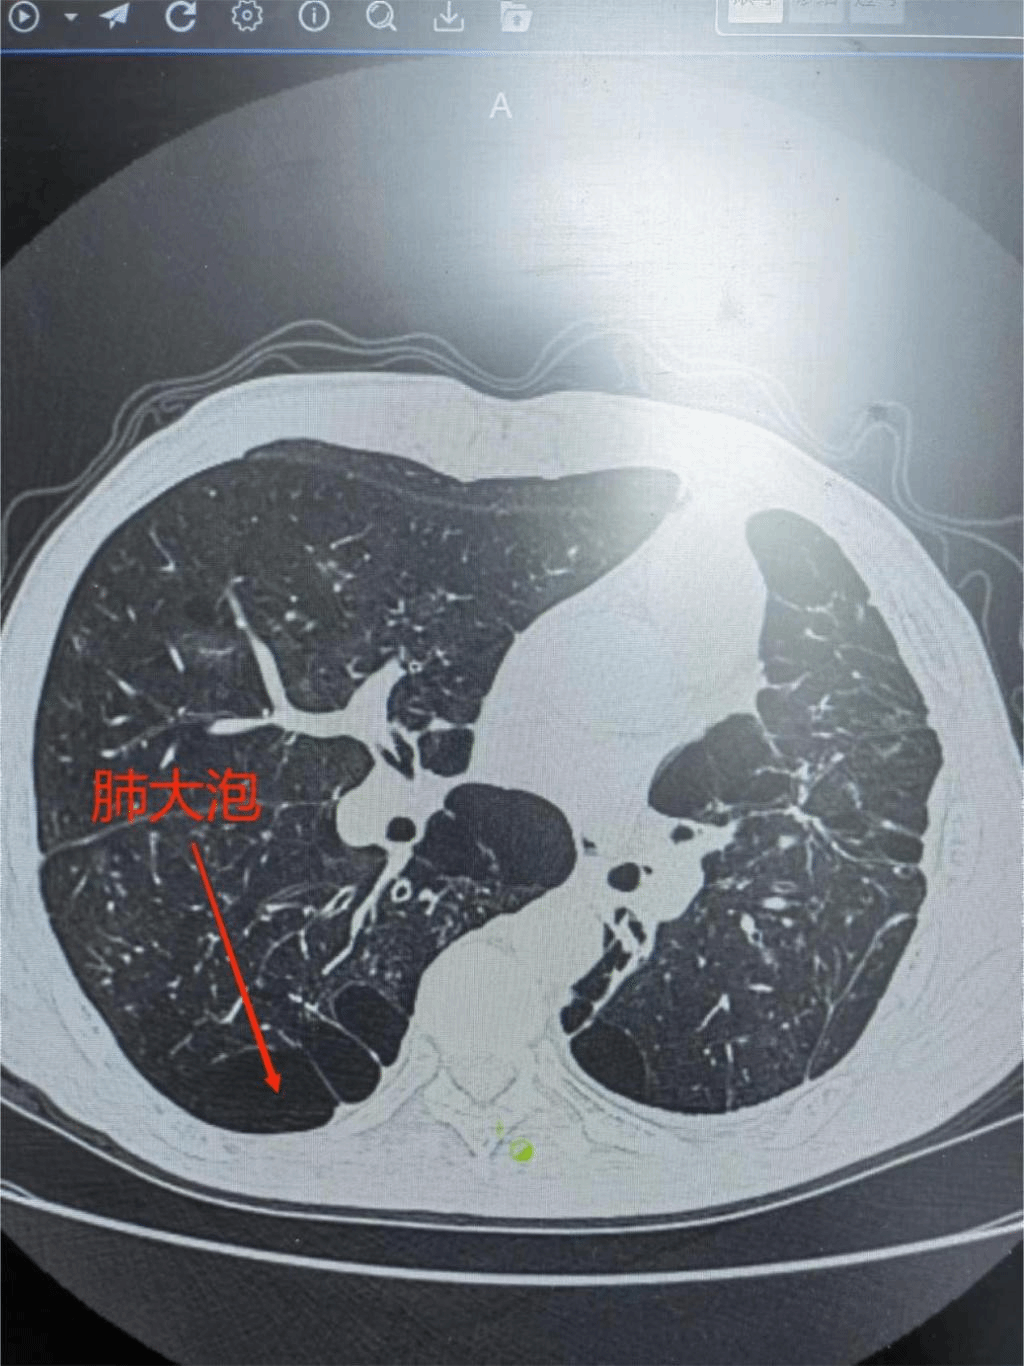

1月29日 第二附属医院呼吸内科付云杰主任团队在胸外科张毅博士、麻醉科李成涛主任的协助下,成功为一例重度慢阻肺患者成功实施经无痛支气管镜双肺EBV活瓣肺减容术,一次性为患者处理了双侧肺大泡。术后患者即可起床活动,饮食照常,完全无痛,胸闷、气喘症状得到明显缓解,效果立杆见影。这是我院第二例支气管镜单项活瓣肺减容术,也是九江地区首例双肺支气管活瓣肺减容术。标志着我院支气管镜介入技术迈入新台阶,将造福更多九江乃至周边区域的患者!